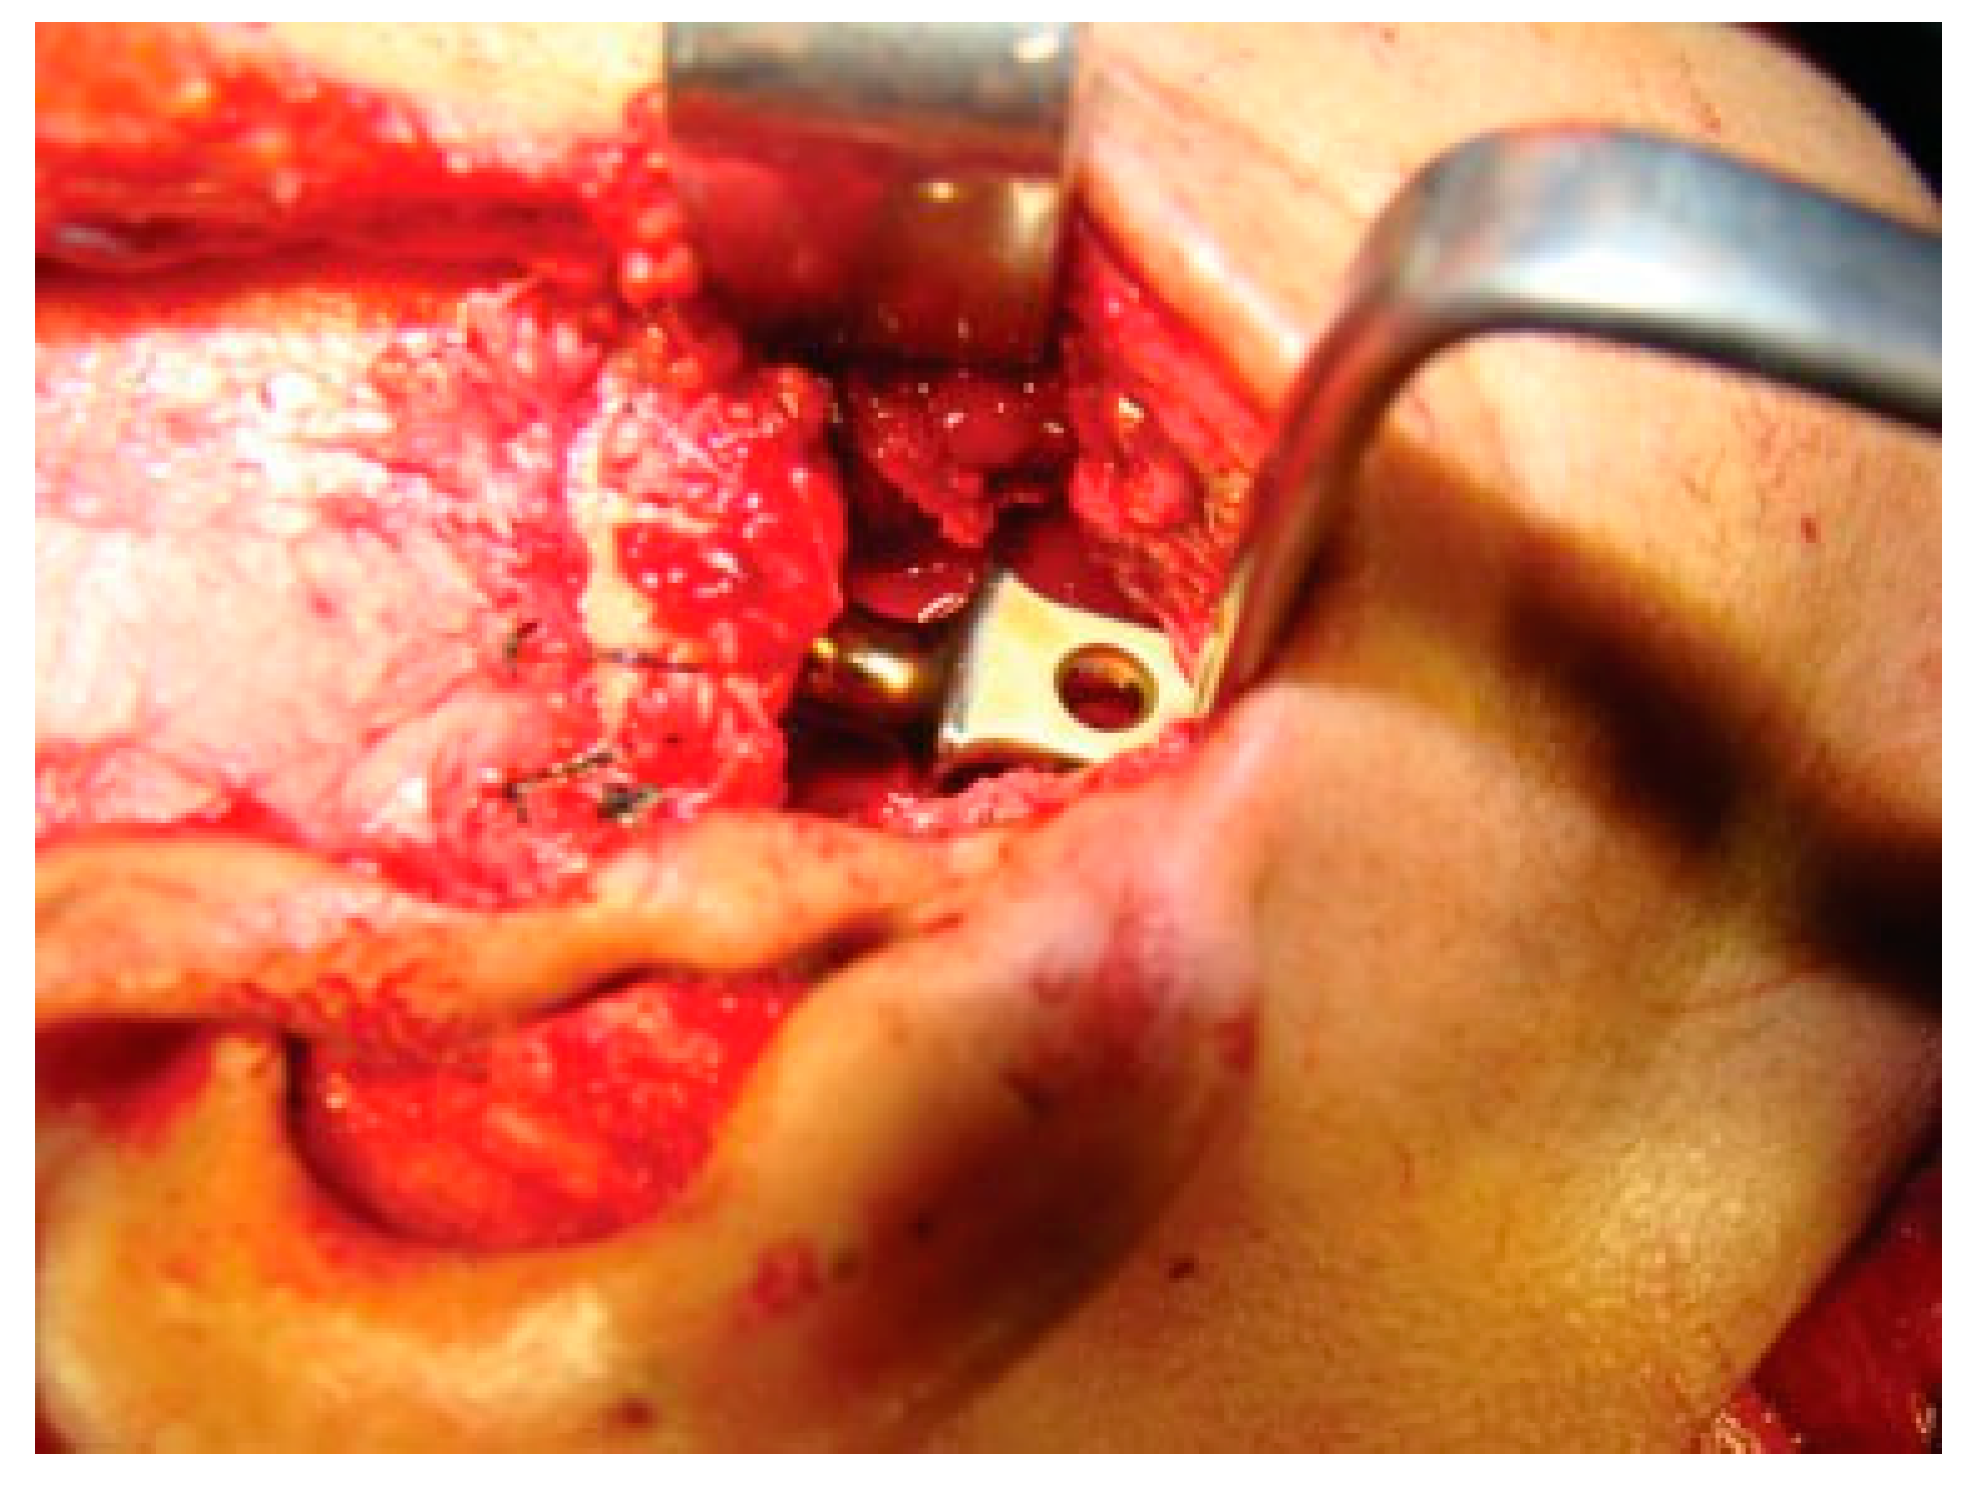

Figure 6. Resected ankylotic chunk with coronoidectomy.

Reconstruction of the TMJ after release of ankylosis assumes paramount importance in terms of restoration of facial form and function. The goals of treatment in all the patients were the release of ankylotic mass, restoration of normal jaw form and function, symmetric growth of the mandible in children, and most importantly the prevention of reankylosis. All interpositional arthroplasties are to some extent the autogenous reconstruction of the morbid ankylotic TMJ after resection of the ankylotic mass. Merriam Webster Dictionary defines reconstruction as the act or process of building something that was damaged or destroyed again. Reconstructive surgery refers to a procedure whose goal is intended to restore form and function in structures deformed or damaged by disease, congenital anomaly, tumor, trauma, or infection (Farlex Partner Medical Dictionary Farlex 2012). The treatment of TMJ ankylosis is individualized based on the severity of ankylosis, age of the patient, and other patient factors. We have outlined our experience following Kaban’s protocol in the management of TMJ ankylosis. It is of paramount importance to obtain passive and maximal mouth opening using this protocol in terms of adequate resection and ipsilateral or contralateral coronoidectomy whenever required followed by aggressive physiotherapy (Figure 5 and Figure 6). Physiotherapy was started on third day postoperatively using Heister mouth gag five times a day during the hospital stay of the patient. This device was purchased by the patient after discharge from the hospital for physiotherapy at home. The MIMO and excursive movements were recorded at various follow-ups for all the patients. No intermaxillary fixation/elastics were applied to any of the patients in the series.